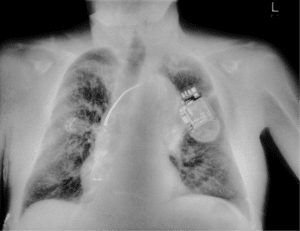

Digital radiography showing a patient, and the region of interest in the right lung is difficult to assess due to overlapping ribs and ECG clip. This is a common challenge in portable ICU imaging.In critical care, clarity isn’t a luxury — it’s a necessity.

Consider the following case: a mechanically ventilated ICU patient shows signs of respiratory distress. A portable chest X-ray is ordered. On the standard digital radiograph, the region of interest in the right lung appears ambiguous. Overlapping ribs and an ECG clip obscure the view — making it difficult to determine whether a consolidative process is evolving. There’s no time to reposition the patient. CT is not an option.

With SpectralDR® technology in the Reveal™ 35C detector, that same exposure produces a soft-tissue-only image — subtracting the bone and medical hardware. The result: a clearly defined area of consolidation in the right lung, enabling a more confident, real-time clinical decision.